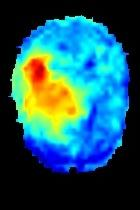

Current unsupervised anomaly localization approaches rely on generative models to learn the distribution of normal images, which is later used to identify potential anomalous regions derived from errors on the reconstructed images. However, a main limitation of nearly all prior literature is the need of employing anomalous images to set a class-specific threshold to locate the anomalies. This limits their usability in realistic scenarios, where only normal data is typically accessible. Despite this major drawback, only a handful of works have addressed this limitation, by integrating supervision on attention maps during training. In this work, we propose a novel formulation that does not require accessing images with abnormalities to define the threshold. Furthermore, and in contrast to very recent work, the proposed constraint is formulated in a more principled manner, leveraging well-known knowledge in constrained optimization. In particular, the equality constraint on the attention maps in prior work is replaced by an inequality constraint, which allows more flexibility. In addition, to address the limitations of penalty-based functions we employ an extension of the popular log-barrier methods to handle the constraint. Comprehensive experiments on the popular BRATS'19 dataset demonstrate that the proposed approach substantially outperforms relevant literature, establishing new state-of-the-art results for unsupervised lesion segmentation.